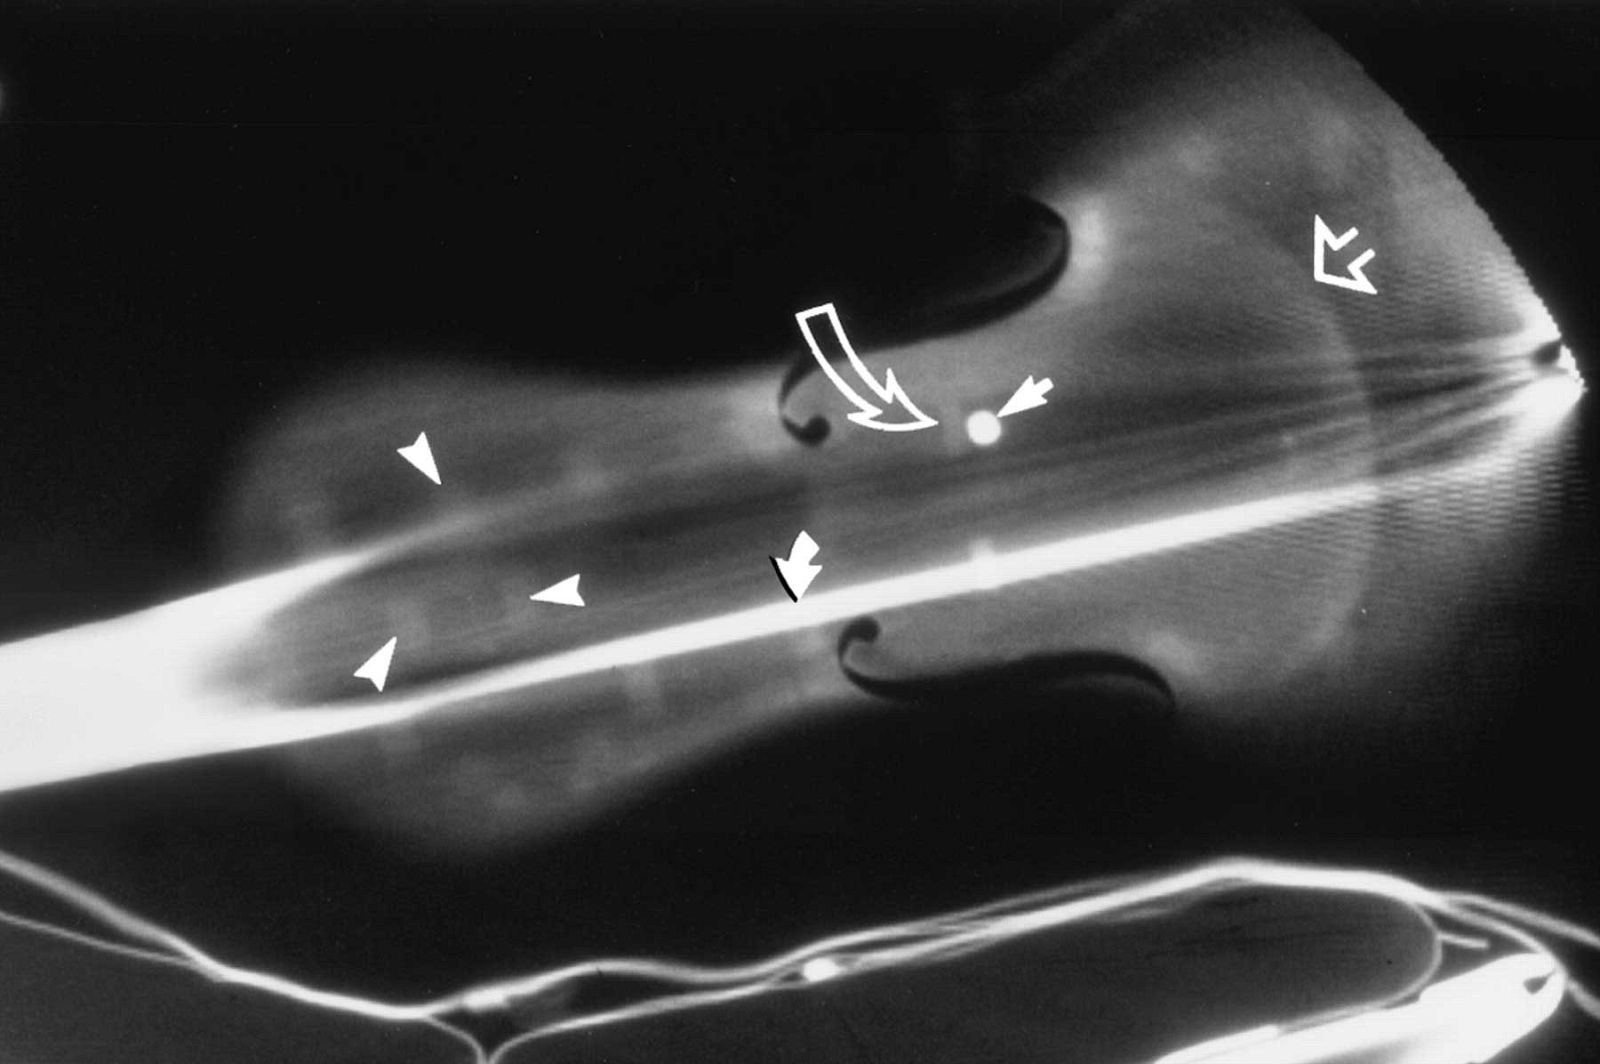

El equipo de investigadores estadounidenses usaron la tomografía computerizada (TC) en este instrumento de más de 300 años para revelar sus secretos. "La TC ofrece un método único, no invasivo, de la imagen de un objeto histórico", afirma Steven Sirr, radiólogo en FirstLight Medical Systems en Minnesota (Estados Unidos), "combinada con maquinaria asistida por ordenador, también ofrece la oportunidad de crear una reproducción con un alto grado de precisión".

El violín original, perteneciente a la Biblioteca del Congreso de EE.UU., fue escaneado y se tomaron más de 1.000 imágenes bajo los rayos X. Después se convirtieron en un formato de archivo para ser leidos por un ordenador en tres dimensiones. Los datos extraídos sirvieron para tallar las piezas de madera cuidadosamente escogidas que fueron luego ensambladas por los dos artesanos expertos en violines y barnizadas a mano.

El responsable de la investigación, violinista aficionado, escaneó por primera vez un violín mediante TC por curiosidad. "Creía que el instrumento no era más que una cáscara de madera que rodea el aire", dijo. "Estaba totalmente equivocado. Había un montón de anatomía interior en el violín".

Después de haber compartido esas primeras imágenes de la TC con Waddle en 1989, los dos pasaron años de exploración de más de 100 violines, entre ellos 29 valiosos instrumentos anteriores a 1827 y otros instrumentos de cuerda para entender mejor su composición.

Para los propietarios de los violines Stradivarius y otros preciados instrumentos, la TC no sólo proporciona una forma definitiva de identificación, también ayuda a establecer un árbol genealógico que pueden aumentar el valor de su inversión. "La TC es útil para medir la densidad de la madera, el tamaño y forma, grosor y graduación de las medidas de volumen," dijo Sirr. "También proporciona un análisis detallado de los daños y la reparación".